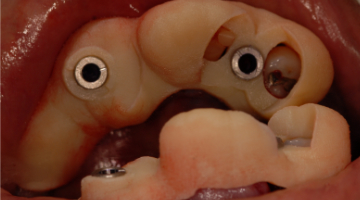

On the day of the procedure, only tooth No. 26 is extracted (figure 4). A full-thickness flap is laid, and implants are placed at site Nos. 23 and 26 just as planned. The final locator abutments are placed and torqued to their final values. A partial denture is fabricated for the patient to wear comfortably during implant integration using the remaining abutment teeth.